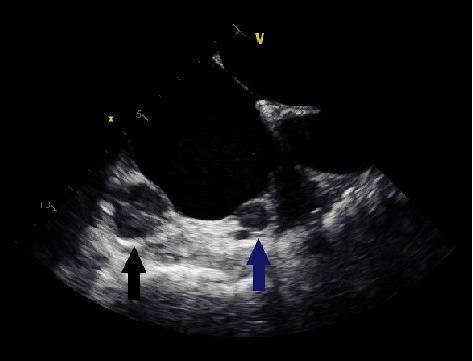

副神经节瘤是肾上腺外染色质细胞瘤。这些肿瘤中有一小部分可以在胸腔中发现,当在心脏中发现时,通常在左心房。在这个病例报告中,我们讨论了一个有SHDB突变的几个副神经节瘤病史的人,他在右心房发现了两个心脏副神经节瘤。

Paragangliomas are extra-adrenal chromaffin cell tumors. A small percentage of these tumors can be found in the thoracic cavity and, when in the heart, are typically in the left atrium. In this case report, we discuss the case of an individual with a history of several paragangliomas with the SHDB mutation who was found to have two cardiac paragangliomas in the right atrium.